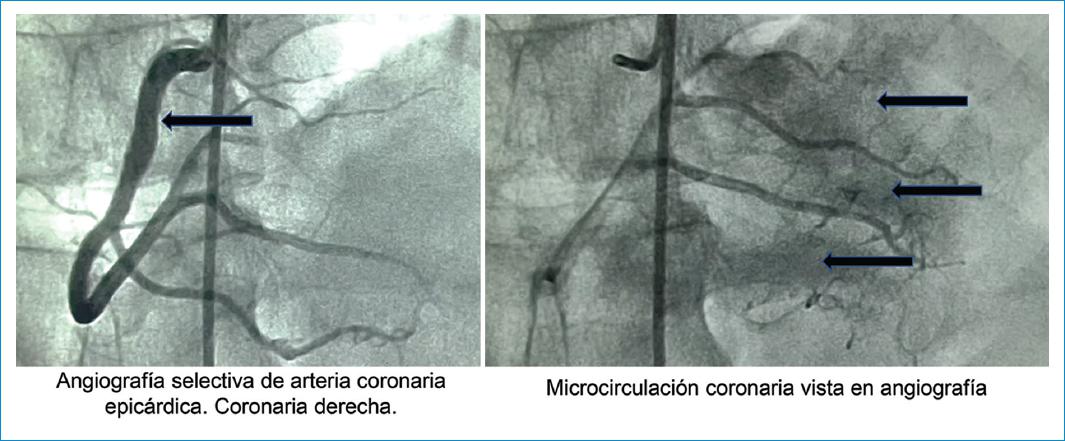

El suministro de sangre a los órganos es perfecto en su arquitectura y es el producto de millones de años de evolución. Cada vez existe mayor evidencia de que la microcirculación coronaria, entendida como los vasos coronarios de diámetro inferior a 300 μm, desarrolla un rol crucial en la fisiopatología de numerosas enfermedades cardíacas. La circulación coronaria, así como todos los lechos vasculares, tienen un comportamiento de árbol o estructura fractal. Dos arterias coronarias mayores que se derivan de la aorta se distribuyen en la superficie epicárdica, y su función es la de actuar como vasos de distribución o de conducción, y aportar gran cantidad de sangre al miocardio. El sistema arterial coronario representa una red continua de vasos funcionalmente distintos y de tamaño decreciente (Fig. 2). Las prearteriolas y las arteriolas constituyen la mayor parte del circuito de resistencia del corazón y se encargan de la regulación y la distribución del flujo sanguíneo para satisfacer las necesidades dinámicas del metabolismo tisular local a través de los capilares coronarios. Los capilares sirven para realizar el intercambio gaseoso y transferir oxígeno y nutrientes al tejido subyacente (Fig. 3). Existen aproximadamente 2500 cardiomiocitos y 2500 capilares por milímetro cuadrado. En reposo, solo una tercera parte de los capilares son perfundidos. Durante el ejercicio, la vasodilatación coronaria resultante favorece un incremento en el reclutamiento capilar y en el flujo sanguíneo local. El endocardio, que representa la capa endotelial de las aurículas, los ventrículos y las válvulas cardiacas, se encuentra desarrollado fenotípicamente distinto del lecho vascular, y por consiguiente no se considera dentro de la microcirculación.

Los estudios han demostrado que aproximadamente la mitad de los pacientes con IM tipo 2 no tienen una EC significativa; es decir, pueden clasificarse como portadores de MINOCA (Myocardial Infarction with Non-Obstructive Coronary Arteries). El diagnóstico de la EMC suele basarse en la evaluación funcional de la microcirculación, que puede realizarse por diferentes métodos. Debido a que la microcirculación coronaria está más allá de la resolución de la angiografía coronaria invasiva o no invasiva (Fig. 2), es necesario el interrogatorio directo de la función microvascular coronaria para establecer el diagnóstico. Existen varios enfoques, no invasivos e invasivos, para la evaluación de la disfunción vasomotora coronaria, cada uno con ventajas y limitaciones. El diagnóstico no invasivo se basa en evaluar la función vasomotora coronaria a través de la medición del flujo sanguíneo miocárdico global y regional en reposo y durante el estrés, la resistencia microvascular y el flujo de reserva coronario (CFR). La PET es el método no invasivo más validado y preciso para la evaluación cuantitativa de la función vasomotora coronaria. La resonancia magnética también se puede utilizar para cuantificar la perfusión miocárdica y descartar enfermedades, como la de takotsubo y la miocarditis. La ecocardiografía Doppler de la arteria coronaria descendente anterior y la TC de perfusión miocárdica dinámica también se han utilizado para estimar el flujo sanguíneo miocárdico. La angiografía coronaria invasiva, al combinar la capacidad de excluir la enfermedad coronaria (EC) obstructiva con técnicas complementarias basadas en catéteres para explorar la fisiología coronaria epicárdica y microvascular, es un enfoque atractivo y moderno para evaluar a los pacientes con EMC. Se encuentran disponibles varias medidas basadas en catéteres: el CFR invasivo en reposo y en respuesta a la vasodilatación de adenosina (independiente del endotelio) o acetilcolina (dependiente del endotelio), el flujo de reserva fraccional (FFR), el índice de resistencia microvascular (CFR/FFR) y el flujo de reserva instantáneo (iFR). Estas mediciones permitirán identificar si la disfunción en la microcirculación es funcional o estructural, y así tomar decisiones terapéuticas mas objetivas.